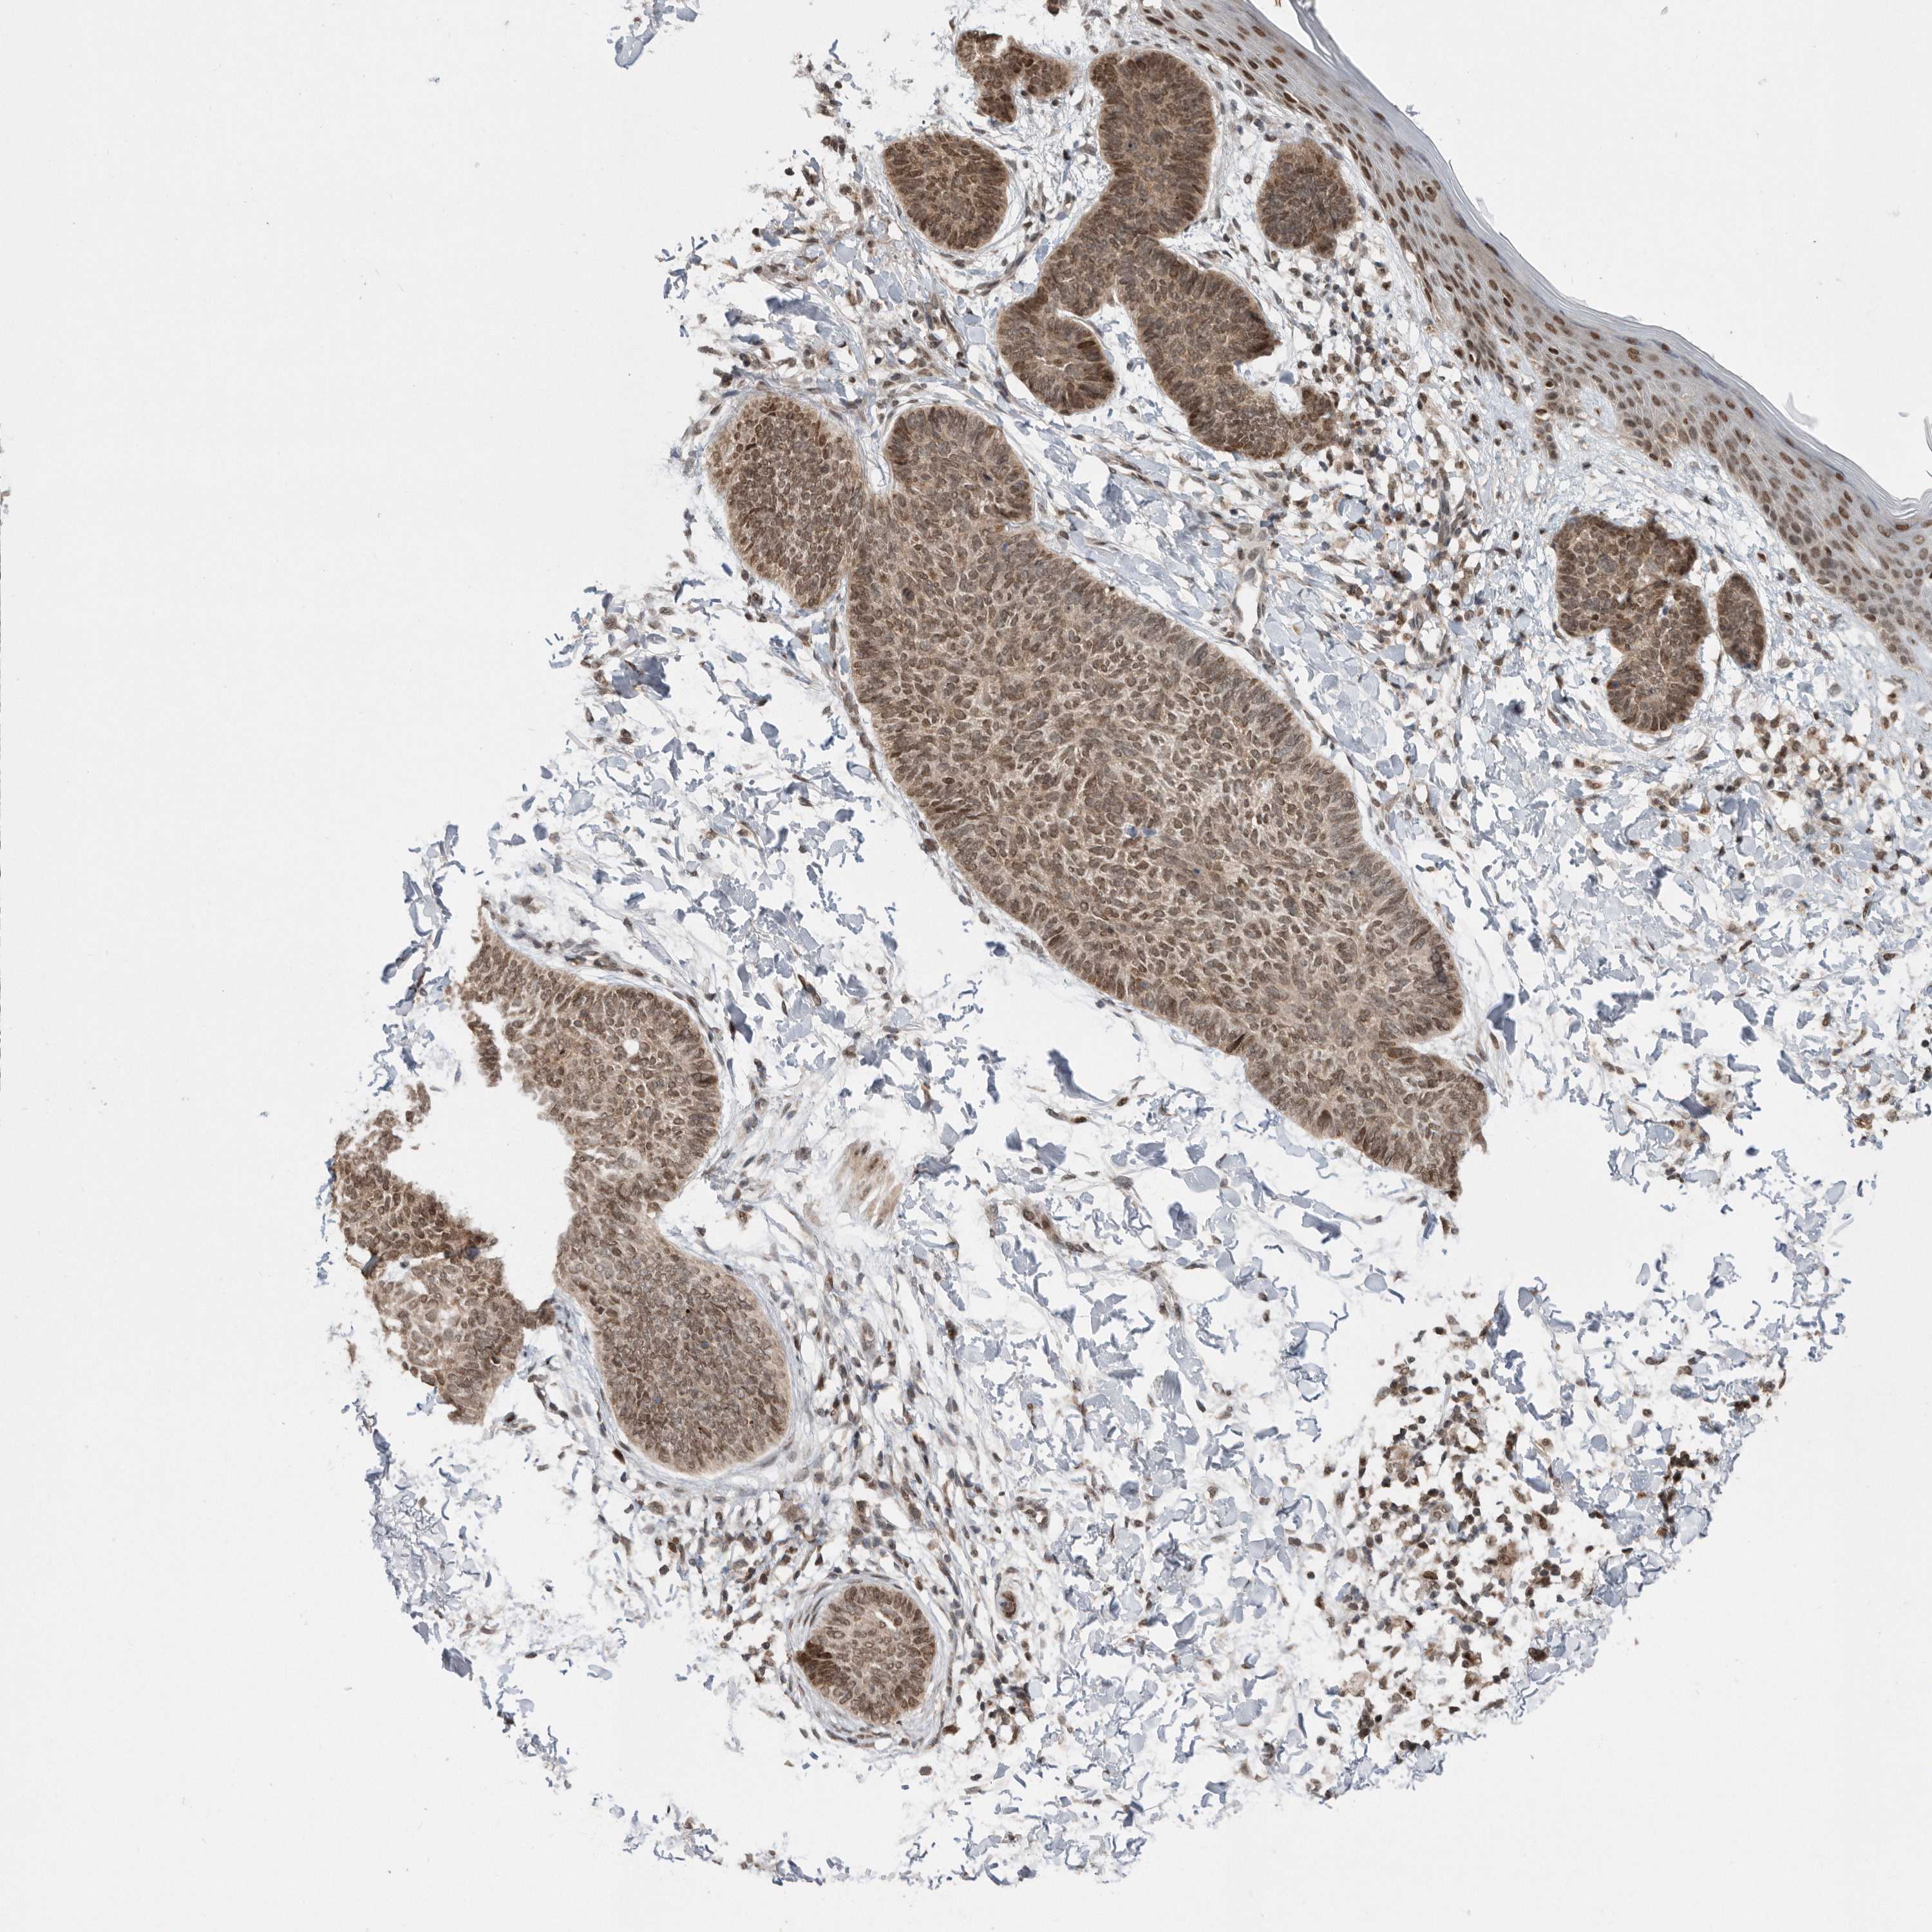

Basal cell and squamous cell cancer

SKIN CANCER - Protein expressioni

A mouse-over function shows sample information and annotation data. Click on an image to view it in a full screen mode. Samples can be filtered based on level of antibody staining by selecting one or several of the following categories: high, medium, low and not detected. The assay and annotation is described here.

Antibody stainingi

Antibody staining in the annotated cell types in the current human tissue is reported as not detected, low, medium, or high, based on conventional immunohistochemistry profiling in selected tissues. This score is based on the combination of the staining intensity and fraction of stained cells.

Each image is clickable and will lead to virtual microscopy that enables deeper exploration of all samples and also displays staining intensity scores, fraction scores and subcellular localization as well as patient and tissue information for each sample.

Antibody CAB034925

Staining

Medium

Intensity

Moderate

Quantity

75%-25%

Location

Nuclear

Cytoplasmic/membranous

Squamous cell carcinoma, NOS